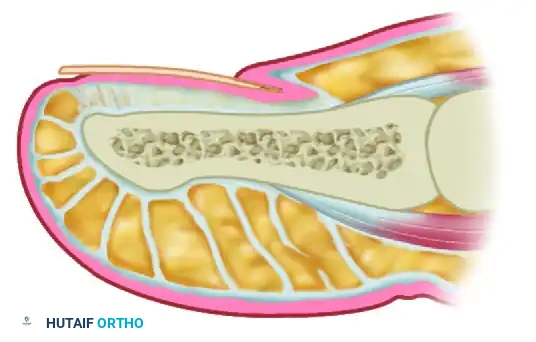

ANATOMY OF THE PERIONYCHIUM

A profound understanding of the perionychial anatomy is the cornerstone of successful surgical intervention. The nail apparatus is a complex, specialized epidermal structure designed to protect the distal phalanx, enhance tactile sensation, and regulate peripheral hemodynamics.

The perionychium comprises the following distinct anatomical entities:

* Nail Plate: The hard, keratinized structure that spans the dorsum of the distal digit. It is produced primarily by the germinal matrix.

* Nail Bed: The highly vascular soft tissue beneath the nail plate, divided into two functional zones:

* Germinal Matrix: Located proximally, extending from the proximal nail fold to the lunula. It is responsible for 90% of nail plate generation. Failure to completely ablate the germinal matrix during surgical management is the primary cause of recurrence.

* Sterile Matrix: Extends from the lunula to the hyponychium. It provides strong adherence to the nail plate and contributes minimally to its thickness.

* Nail Folds: The cutaneous structures surrounding the nail plate, including the proximal nail fold (terminating in the eponychium/cuticle) and the lateral nail folds (paronychium).

* Hyponychium: The specialized epidermal junction between the distal nail bed and the volar skin of the digit, serving as a barrier against subungual infection.

Surgical Warning: The germinal matrix extends proximally beneath the eponychium for a distance of 5 to 8 mm. Surgical or chemical matrixectomy must reach this proximal recess to ensure complete ablation of the nail-forming tissue.